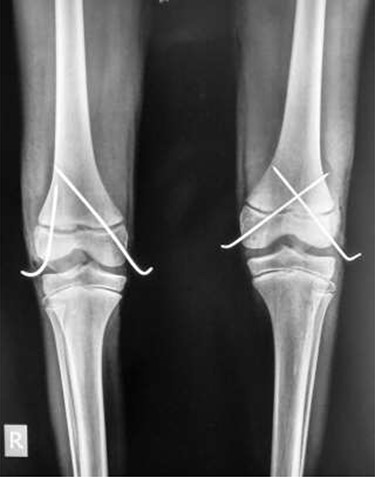

In theatre, general anaesthesia and prone positioning were performed. Closed reduction with gentle traction was achieved, followed by gradual flexion of the knee (Wilkin’s Manoeuvre). The physeal fragment was reduced with both thumbs, and reduction checked under mobile X-ray—good realignment was confirmed. Final fixation was achieved with percutaneous smooth K-wires in a cross construct (Figs 2, 3A and B). An anterior slab maintaining knee flexion was then applied. This process was repeated contralaterally. After 24 h and with adequate analgesia, bilateral foot-drop was noted. Bilateral posterior slabs were then applied.

Frontal view of both knees after closed reduction and K-wire fixation